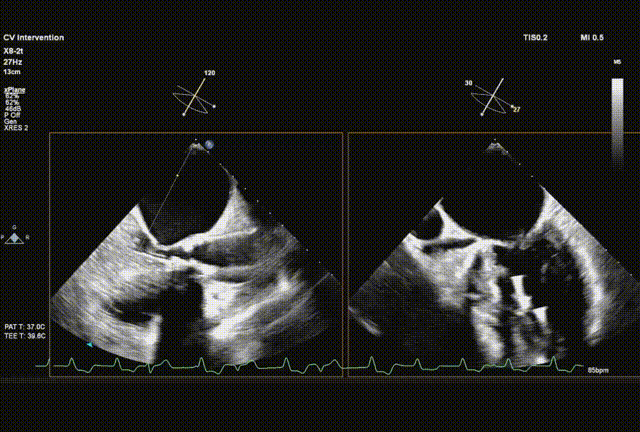

采样线扫到无窦,180起搏,长轴视图下快速释放到工作位

超声从左至右,最后无冠窦侧评估深度合适

起搏下完全释放瓣膜

左右旋转系统并前送,观察无瓣膜移动,回撤导丝后再撤出系统

术后超声评估,未见瓣周漏,平均跨瓣压15 mmHg,血流速度197 cm/s